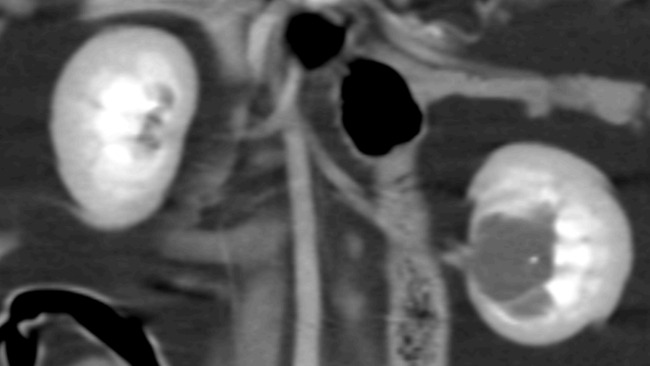

Ptyś jest kotem, który kiedyś żył na ulicy. Pewnego dnia zabrałem go ze sobą do domu i tak już został. Pokochałem go i zapewniłem najlepszą opiekę jaką byłem w stanie. Około dwa miesiące temu, przy okazji rutynowych badań, przed zabiegiem usunięcia zębów, okazało się, że cierpi na wodonercze. Czym w skrócie jest to wodonercze? Jego moczowody nie są do końca drożne. Ptyś kuwetę odwiedza często, mimo to, mocz gromadzi się w jego nerkach, powodując stan zapalny i ból. Jego nerki są powiększone i rozepchane nadmiarem substancji, której nie powinno tam tyle być. Skąd to się wzięło? Nie wiadomo. Kamieni - najbardziej prawdopodobnych, nie widać. Ptyś był przebadany na wiele sposobów. Może to być nawet wada genetyczna w postaci zrostu lub zwężenia moczowodu.

Jego nerki mimo to pracują, lecz bardzo się boję, że nie na długo. Obraz jaki dała nam tomografia z kontrastem sugeruje konieczność wykonania zabiegu jakim jest bajpas nerki. To w skrócie sztuczny moczowód. Dzięki niemu mocz będzie mógł zostać odprowadzony z nerki, aby ona mogła wrócić do normalnej wielkości i nie zagrażać już Ptysiowi. Niestety zabieg jest bardzo drogi. Kosztuje 11 tysięcy złotych. Cena samego "sztucznego moczowodu" jest koszmarnie wysoka, gdyż jest dostępny tylko u jednego producenta w Stanach Zjednoczonych. Zabieg jest u nas stosunkowo młody. Dr Sylwia Lew-Kojrys, która specjalizuje się chorobach nerek, wykonuje go od zaledwie 5 lat. Na dzień dzisiejszy jest dosłownie garstka lekarzy, która tak skomplikowanego zabiegu się w Polsce podejmuje. Potrzebujemy środków na operację, wizyty kontrolne oraz transport. Zabieg, jeśli się uda, odbędzie się w Olsztynie w Klinice Weterynaryjnej Lew. Do tej pory wszystko płaciłem ze swojej kieszeni lub korzystałem z ogromnej pomocy mojego współlokatora, bardzo wykorzystując jego dobre serce i cierpliwość.

Do zrzutki załączam wyniki krwi oraz tomografię Ptysia.